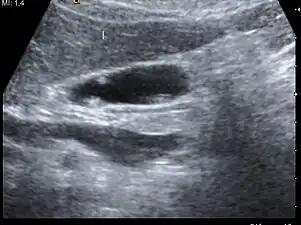

Adenomyomatosis describes a diseased state of the gallbladder in which the gallbladder wall is excessively thick, due to proliferation of subsurface cellular layer. It is characterized by deep folds into the muscularis propria. Ultrasonography may reveal the thickened gallbladder wall with intramural diverticulae, called Rokitansky-Aschoff sinuses.[3]

Diagnosis is typically by ultrasound or CT imaging.